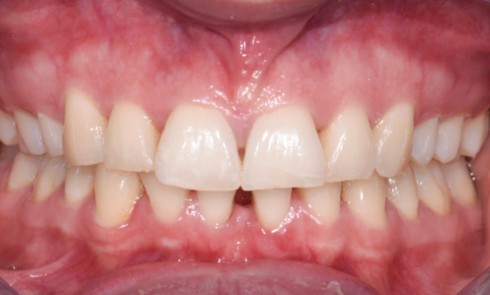

Article réservé à nos abonnés Parodontite stade 2 grade A

Qu’est-ce qu’une parodontite stade II grade A selon la classification de Chicago 2017 ? Il s’agit d’une parodontite modérée à progression lente [1]. Les outils...